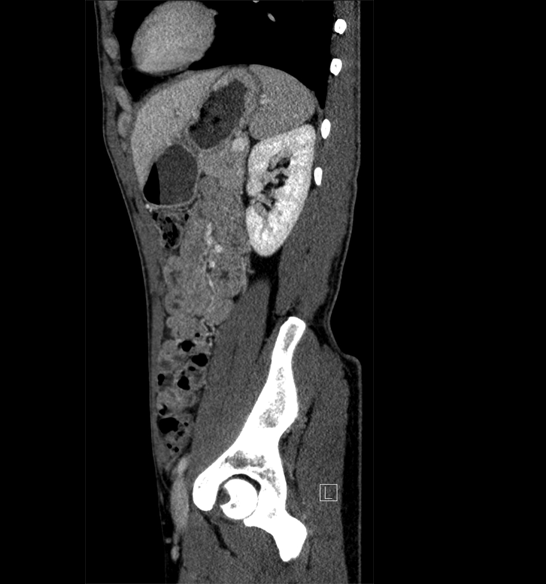

Body

Covers abdominal CT anatomy.